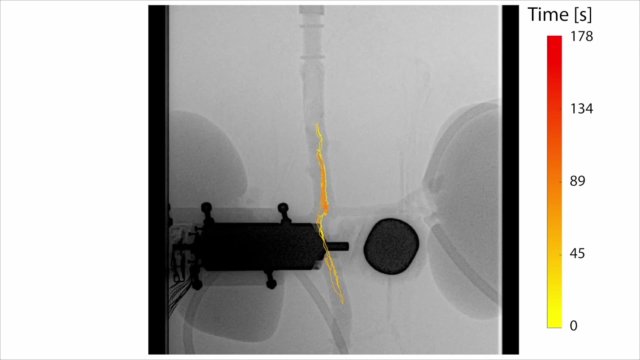

In the experiment, the researchers used a robotically controlled rotating magnetic field to control the millirobots wirelessly. With an X-ray machine, they were able to localise the millirobot while steering through the aorta. The researchers maintained a maximum arterial flow of 120 ml per minute inside the aorta. But with a stronger magnetic field, the millirobots should be able to overcome a greater blood flow. The millirobots performed stable straight runs with and against the flow, and also with multiple robots at the same time.